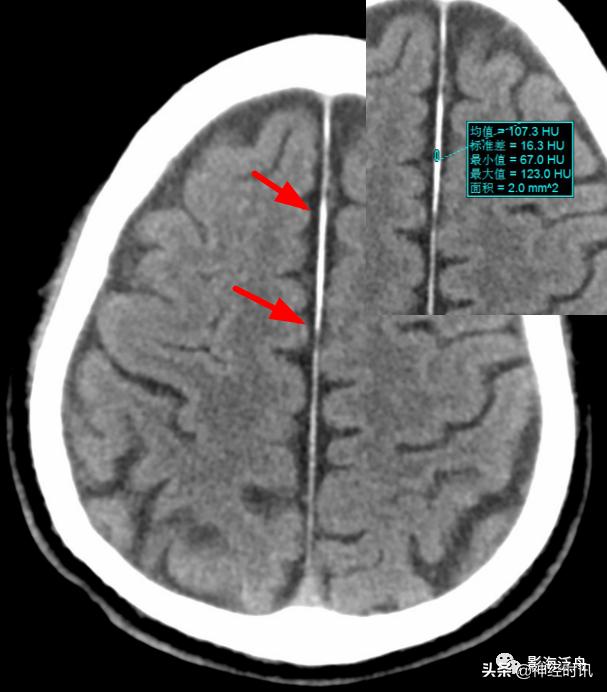

典型的大脑镰前部少量蛛血,血肿的边缘毛糙(红箭)且抵达胼胝体膝部的前缘(黄箭头)。4天后复查头颅CT平扫,相应部位少量蛛血基本吸收。

另一例表现类似的大脑镰前部少量蛛血,血肿的边缘总是有一种毛毛糙糙的感觉(红箭)。

国内一些文献将大脑镰一侧不对称的高密度影被定义为“偏密征”,并认为上述影像学特征是诊断大脑镰旁少量蛛网膜下腔出血的可靠征象,可提示出血部位位于“偏密征”附近,或继发于邻近的其它颅内损伤。

本例颅脑外伤患者的大脑镰右旁可见“偏密征”,但这个血肿的边缘非常光滑(红箭)且未延伸至邻近脑沟内,边缘似乎还带有一些张力感,笔者觉得此例诊断为大脑镰旁硬膜下血肿更合适。但不管怎么说,“偏密征”用于鉴别是否存在局限性的脑外伤还是很有用的。